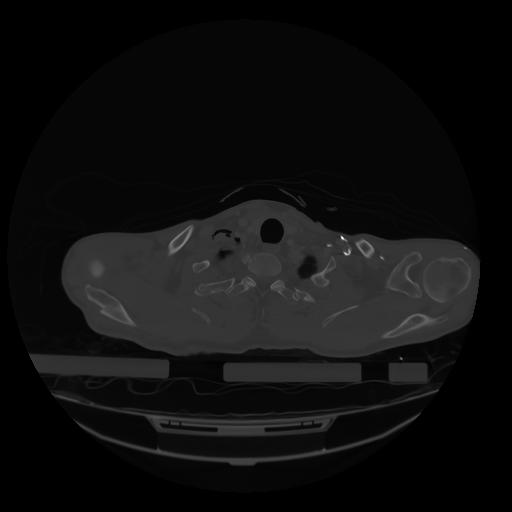

28 CUERPO,CE,Vol,2.0,CUERPO,,